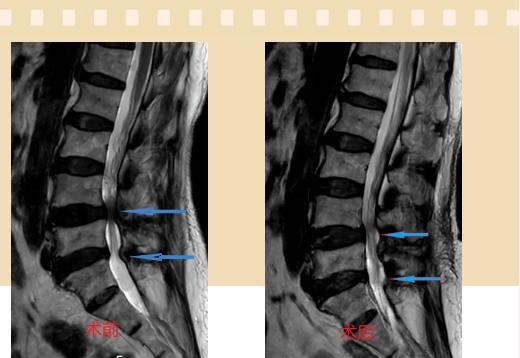

入院后李鵬副主任醫(yī)師為其進(jìn)行了詳細(xì)的查體,完善了術(shù)前的檢查,明確診斷為:腰椎管狹窄癥(L4/5、L5/S1),病人合并2型糖尿病,請(qǐng)內(nèi)分泌科會(huì)診,穩(wěn)定血糖后,麻醉科會(huì)診病人,排除手術(shù)禁忌,李鵬為病人制定了手術(shù)方案:?jiǎn)蝹?cè)入路雙側(cè)減壓(ULBD)。

手術(shù)采用三個(gè)微創(chuàng)小切口,兩個(gè)節(jié)段減壓手術(shù)時(shí)間2.5小時(shí),出血50ml。術(shù)后2天腰圍保護(hù)下床活動(dòng),術(shù)后5天順利出院。

傳統(tǒng)腰椎管狹窄癥的手術(shù)治療,往往需要切開(kāi)減壓,同時(shí)需要內(nèi)固定融合術(shù),創(chuàng)傷很大,同時(shí)可能需要輸血,臥床時(shí)間較長(zhǎng),病人合并糖尿病,感染風(fēng)險(xiǎn)也高,而本次采用的UBE-ULBD手術(shù)切口更?。悠饋?lái)約3cm,如果是單節(jié)段狹窄只需要不到2cm切口)、創(chuàng)傷更小,術(shù)后恢復(fù)較快,可以更早地恢復(fù)正?;顒?dòng)。

此外,手術(shù)保留了病變節(jié)段的穩(wěn)定性,是一種微創(chuàng)的椎管減壓手術(shù),能通過(guò)切除部分椎板、關(guān)節(jié)突關(guān)節(jié)、黃韌帶來(lái)解除神經(jīng)根和硬膜囊的壓迫,不需要額外行腰椎內(nèi)固定術(shù),不需要螺釘及融合器的植入,病人術(shù)后腰椎的活動(dòng)度不受影響。(盧   闖  劉   旭   袁錦鈺)